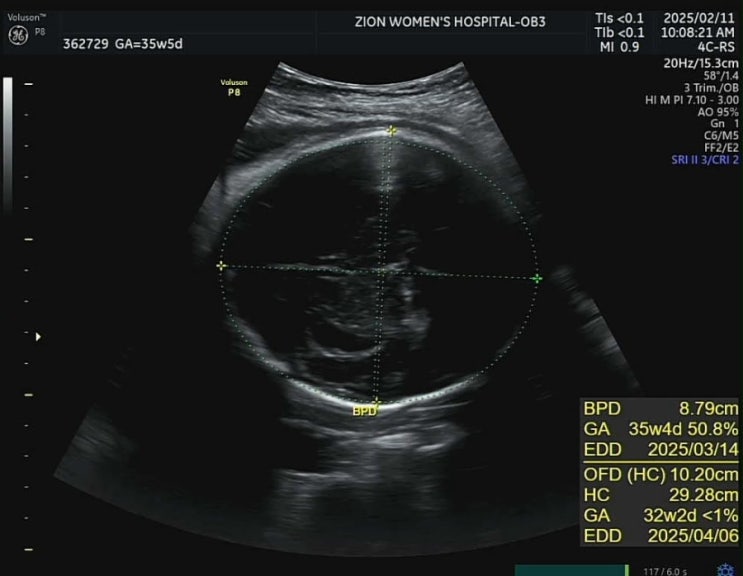

[임신35주] 아기빨래시작 / 식세기구입 / 막달검사 / D-30

임신 34주 새해 첫 달 마지막날에 34주가 되었다. 34주라니..? 34주라니..!!!!! 눈이 많이와서 한동안 외출...